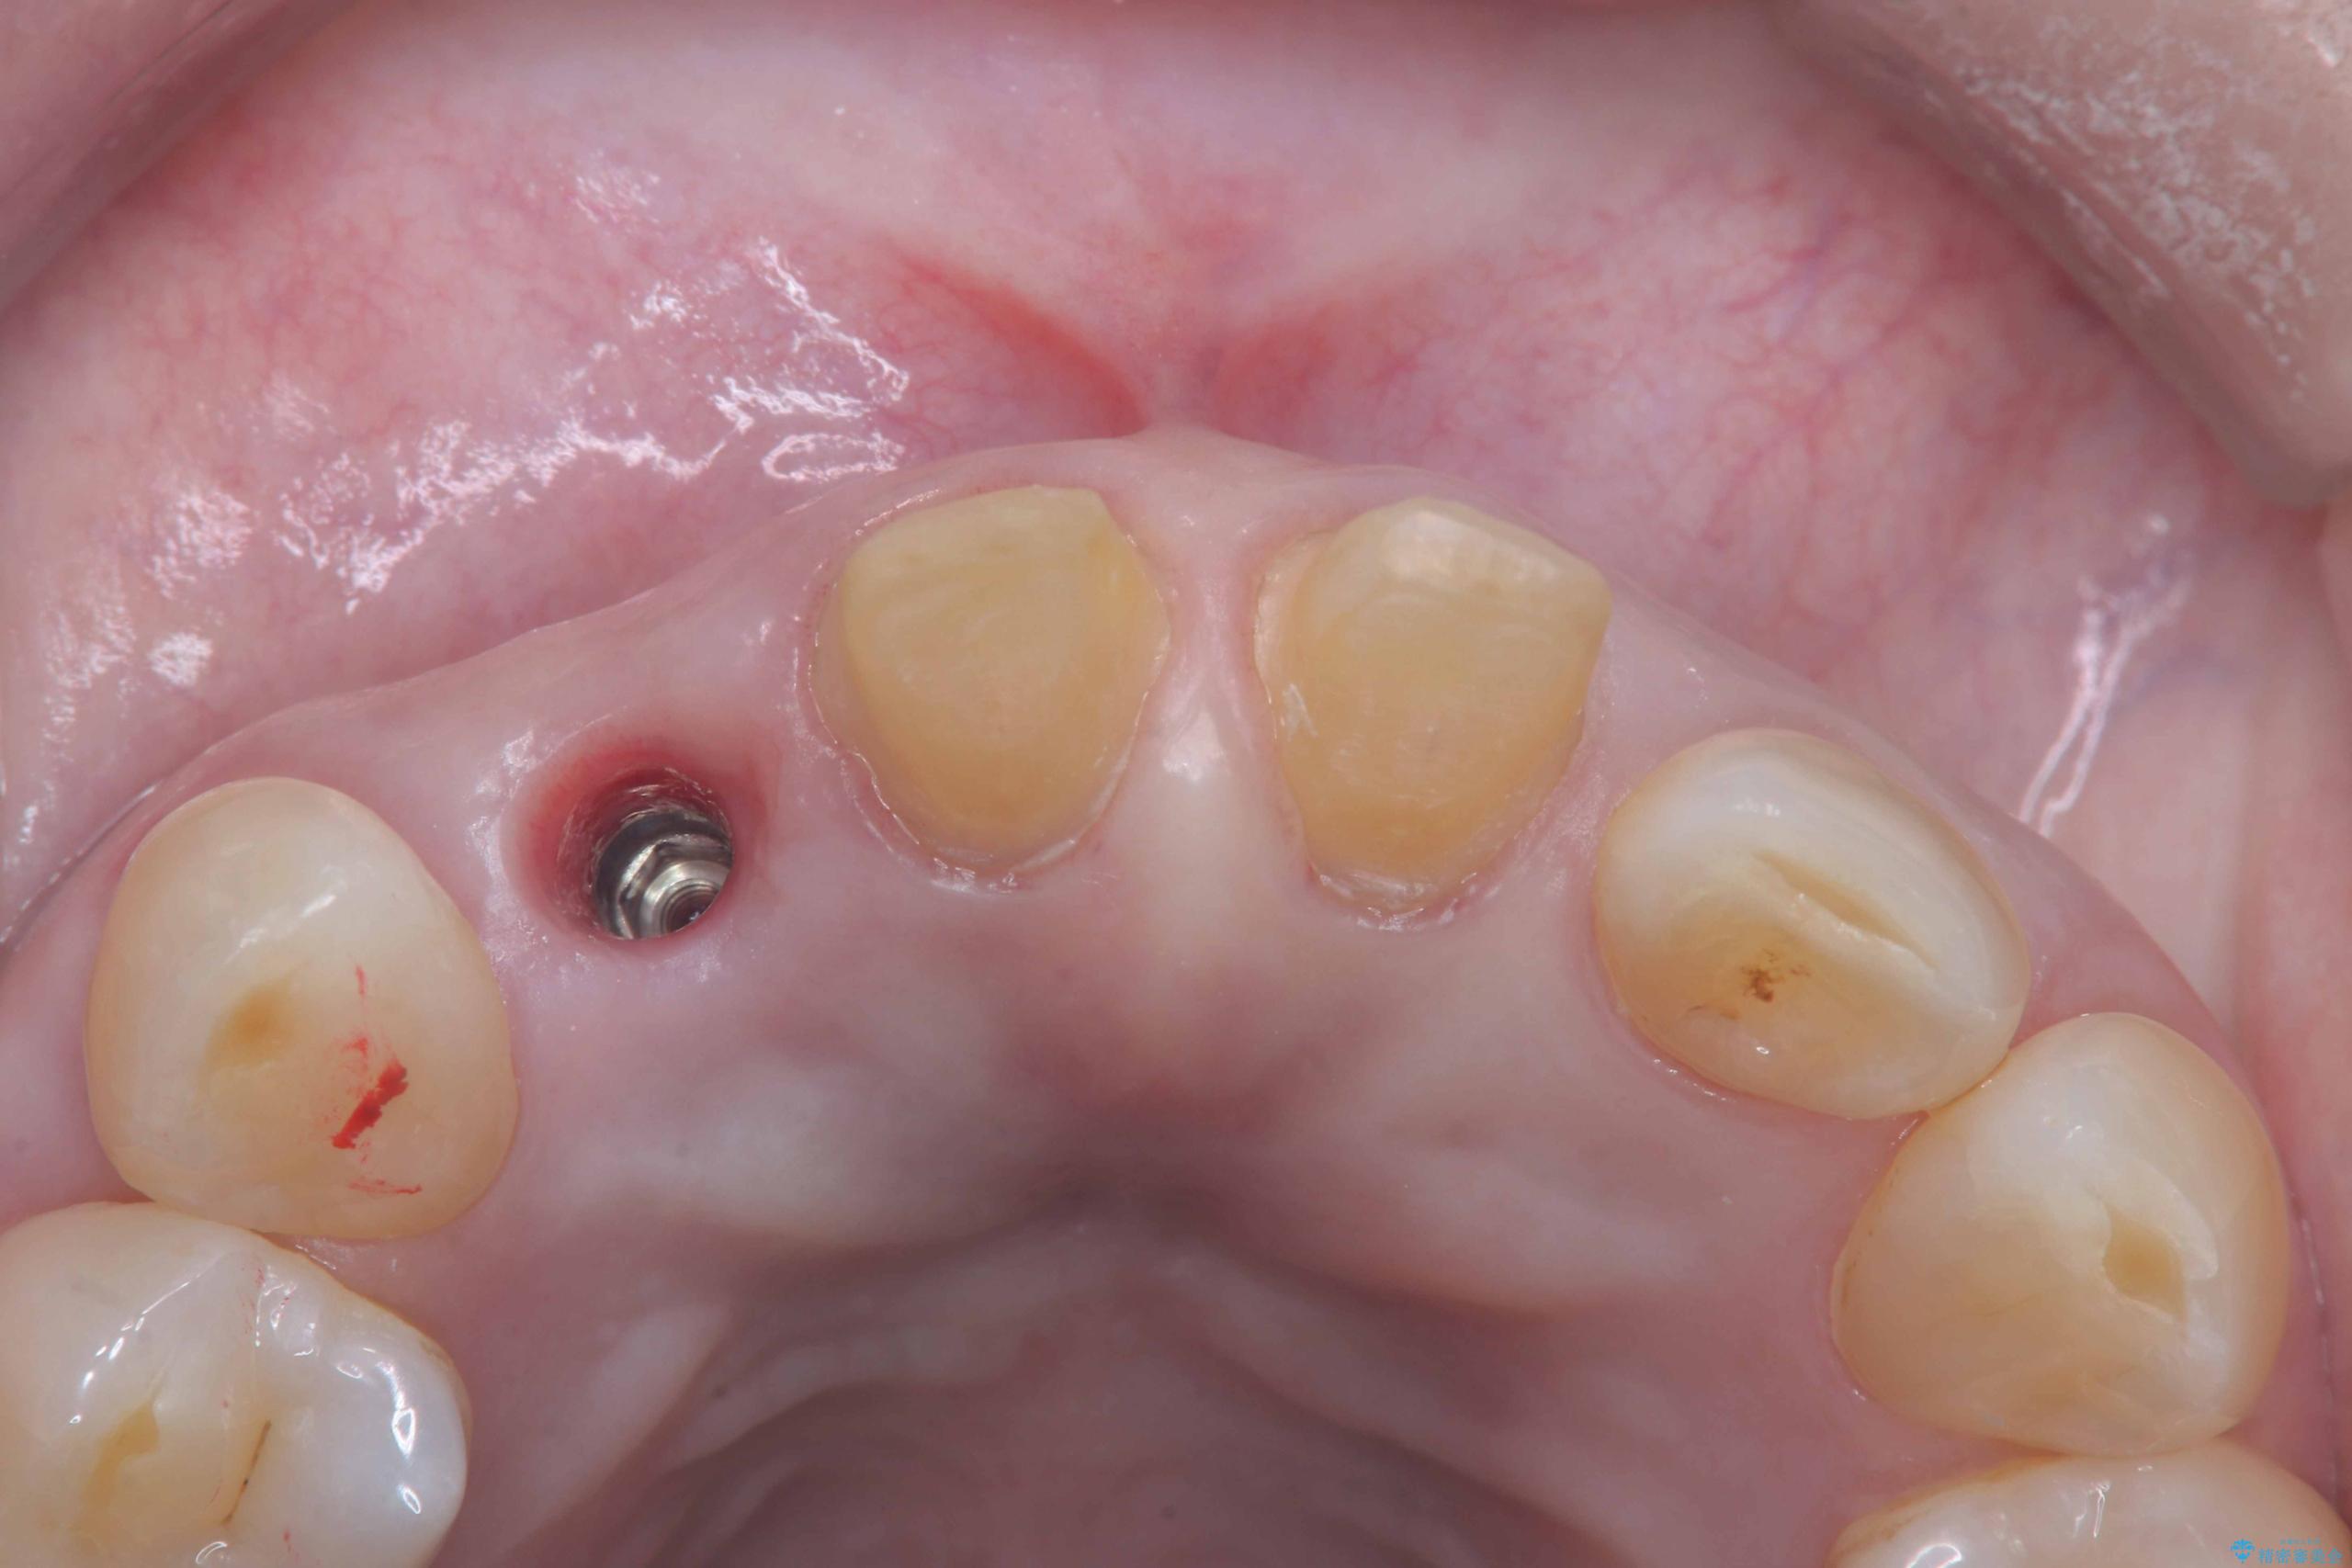

- 前歯の隙間とへこみが気になり、特に舌で触ると気になってストレスを感じるとのことで来院された患者様です。

そのため今回は、右上2番を抜歯し、右上1番および左上1番をオールセラミッククラウンで審美的に修復しました。

また、オペ当日には仮歯まで装着するため、見た目を気にせず普段通りの生活を送ることができます。